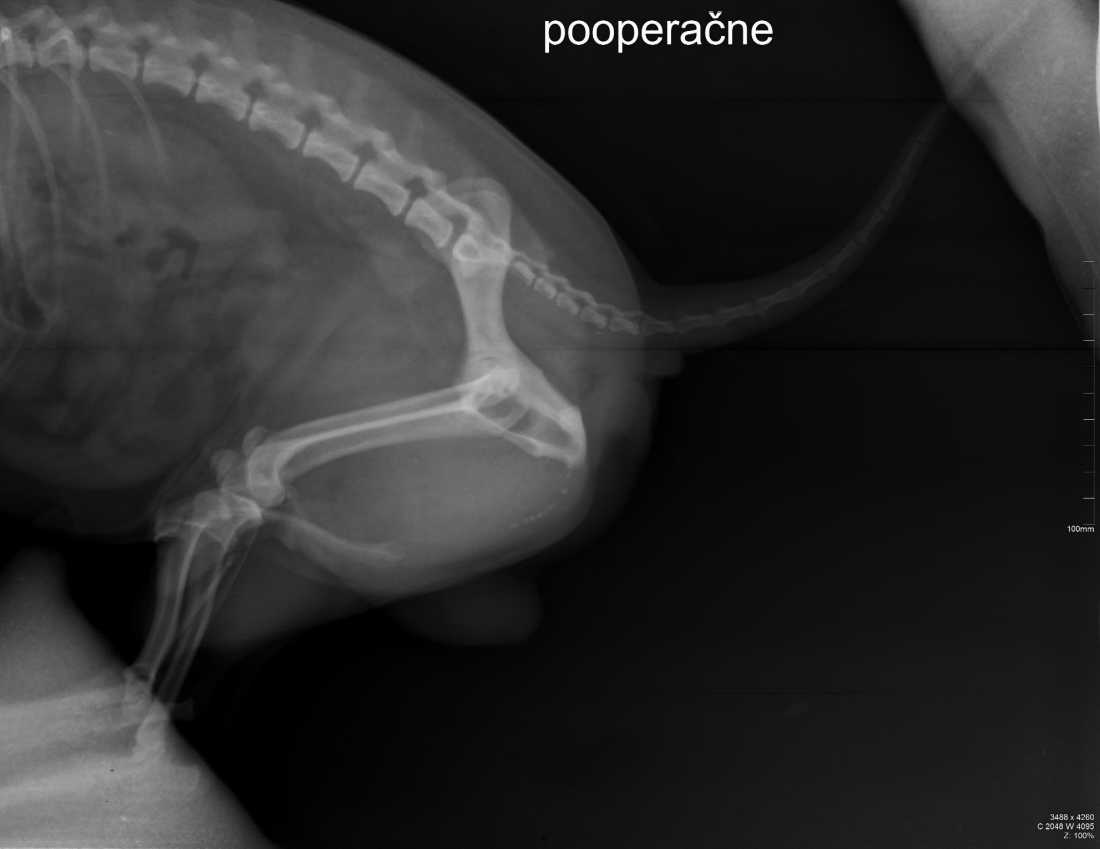

lateral recumbency

dog (square vertebrae)

male (os penis)

flexura urethralis

particles with radiopacity of bone

8-9

irregular shape

urinary stones